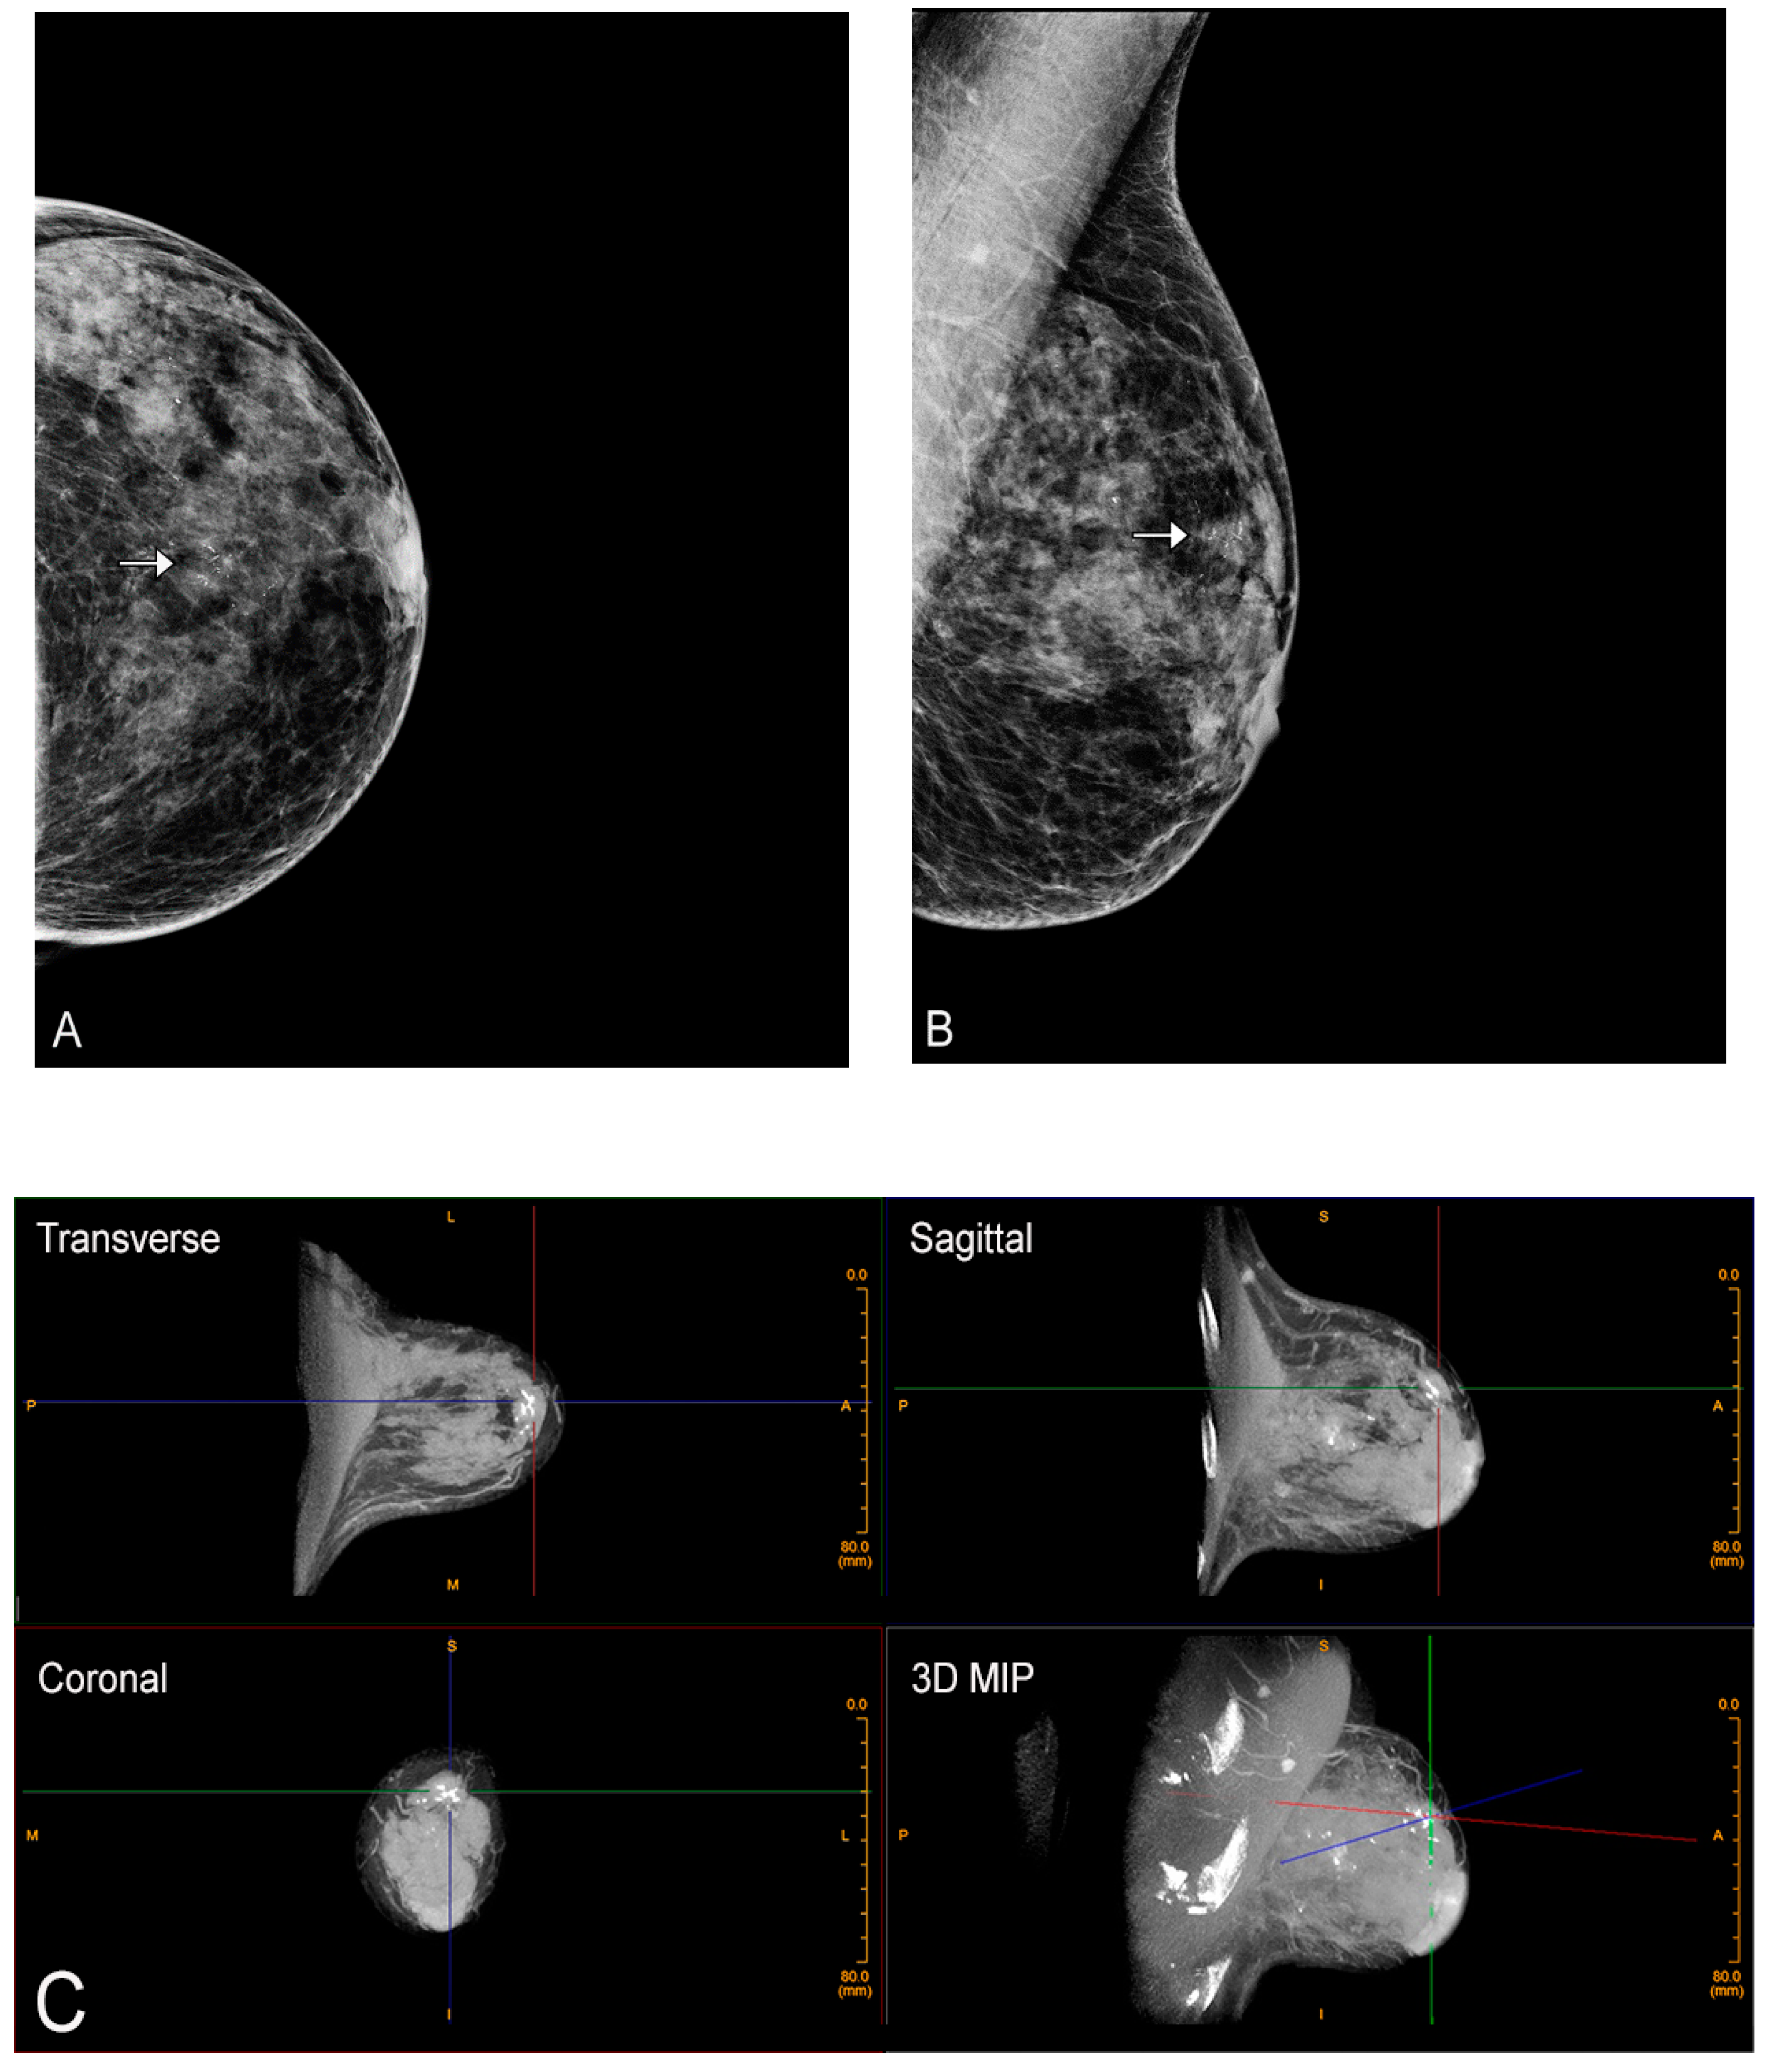

2. Cone-Beam Breast Computed Tomography